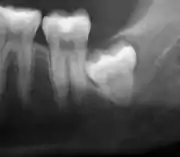

Impacted wisdom teeth are classified by their direction of impaction, their depth compared to the biting surface of adjacent teeth and the amount of the tooth's crown that extends through gum tissue or bone. Impacted wisdom teeth can also be classified by the presence or absence of symptoms and disease. Screening for the presence of wisdom teeth often begins in late adolescence when a partially developed tooth may become impacted. Screening commonly includes a clinical examination as well as x-rays such as panoramic radiographs.

The diagnosis of impaction can be made clinically if enough of the wisdom tooth is visible to determine its angulation, depth, and if the patient is old enough that further eruption or uprighting is unlikely. Wisdom teeth continue to move to the age of 25 years old due to eruption, and then continue some later movement owing to periodontal disease.[18]

If the tooth cannot be assessed with clinical exam alone, the diagnosis is made using either a panoramic radiograph or cone-beam CT. Where unerupted wisdom teeth still have eruption potential several predictors are used to determine the chance of the teeth becoming impacted. The ratio of space between the tooth crown length and the amount of space available, the angle of the teeth compared to the other teeth are the two most commonly used predictors, with the space ratio being the most accurate. Despite the capacity for movement into early adulthood, the likelihood that the tooth will become impacted can be predicted when the ratio of space available to the length of the crown of the tooth is under 1.[5]: 141